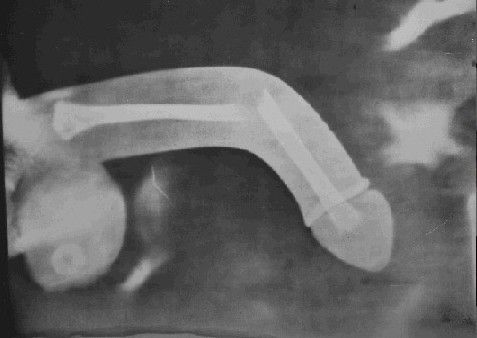

检查过后,小陈被诊断为生殖器断裂,即海绵体白膜破裂伤。重庆红楼医院男科专家傅群建表示,这类病症多发生在夫妻生活中急剧改变体位时,患者当时会明显感觉到疼痛,随后会发生肿胀。

据了解,生活中,像小陈这样遭遇生殖器折断伤的情况并不多见,但一旦发生,对男性健康的损害非常大,“如果处理及时,基本上都可以恢复正常功能,如果耽误时间太久,对男性性功能会造成难以估量的影响,最严重的只能切除。”重庆红楼医院男科专家傅群建说,所幸小陈来院还不算太晚,通过外科手术处理,可以恢复正常功能。